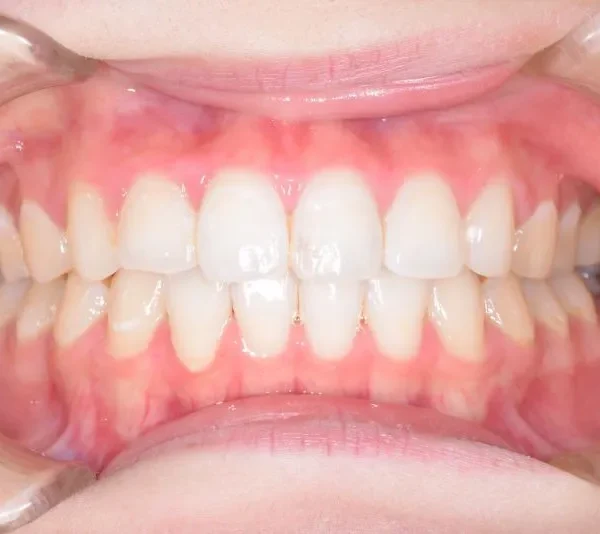

初診時年齢 19~29歳 (女性) 主訴 上下がガタガタ・出っ歯

診断名 叢生・上下顎前突 装置名

マルチブラケット装置

リンガルブラケット矯正装置

歯科矯正用アンカースクリュー

抜歯の有無 非抜歯 治療期間・通院回数 1年 6ヶ月

費用 670000円(税込) 費用内訳 ブラケット・

再治療の時は、上の歯は前から見えにくいオリジナル固定装置、下の歯はマルチブラケット装置を使用し、治療しました。

治療回数62回、1年6ヶ月の治療期間で矯正治療を終了しました。